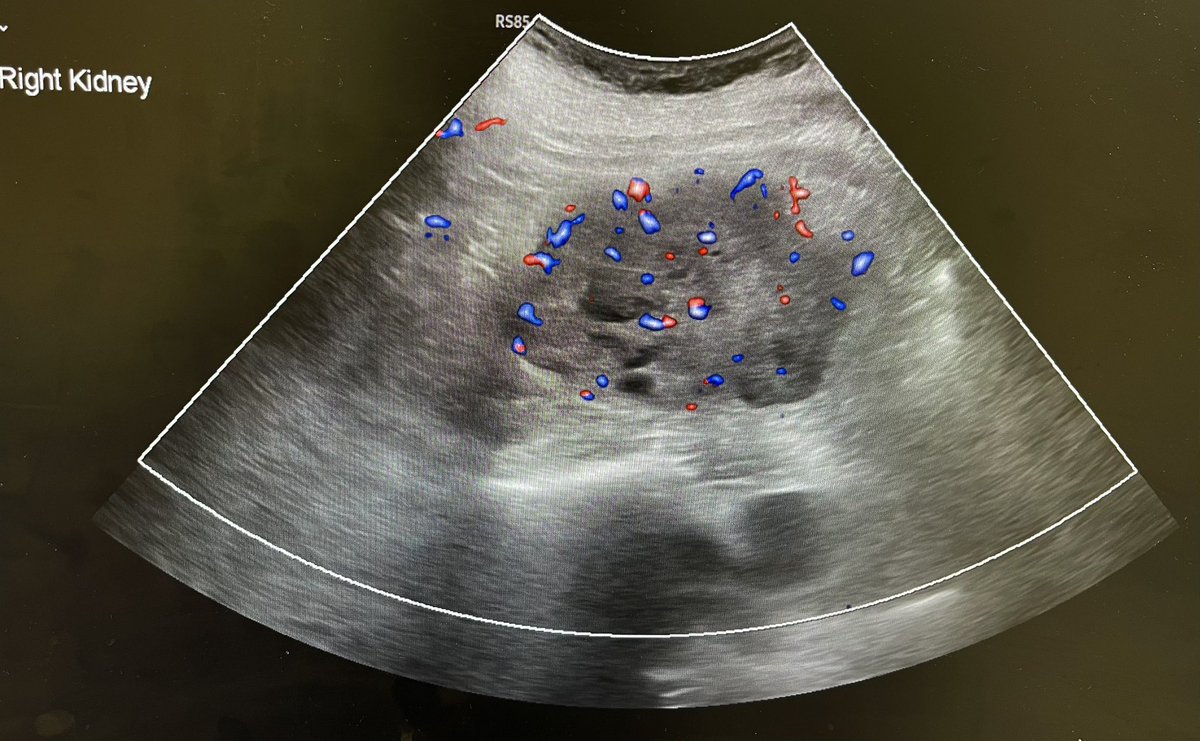

Cortical scarring. @Rad_Munagi